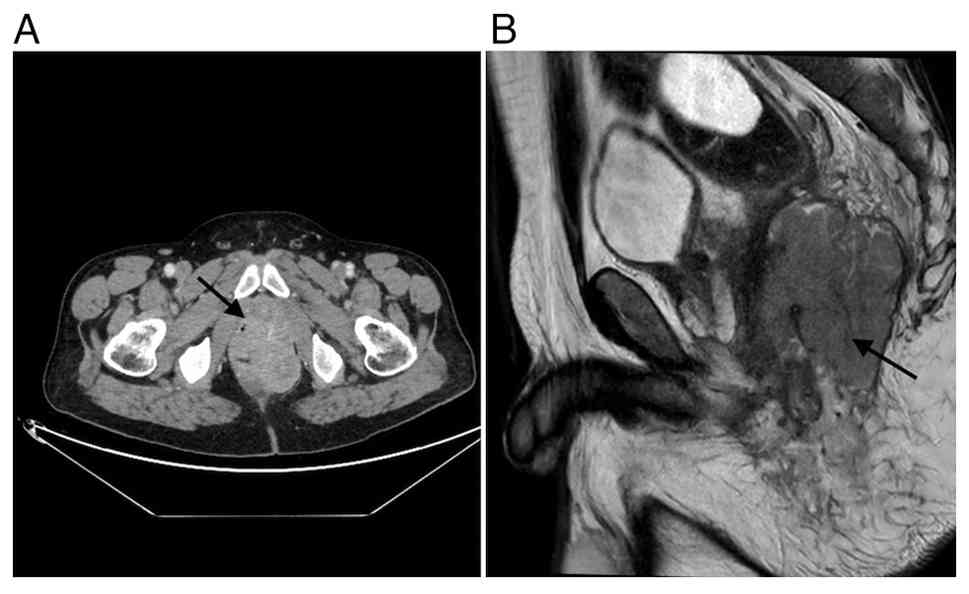

Repeat imaging demonstrated significant tumor regression, although a residual abscess persisted (Fig. 3). The mass remained inseparable from adjacent structures but showed no involvement of the bladder. Based on radiological improvement and the absence of metastatic disease, the tumor board recommended surgical resection with curative intent.

(A) CT scan and (B) MRI findings after

radiotherapy treatment (the arrow indicates the tumoral mass).

Figure 3.

(A) CT scan and (B) MRI findings after radiotherapy treatment (the arrow indicates the tumoral mass).